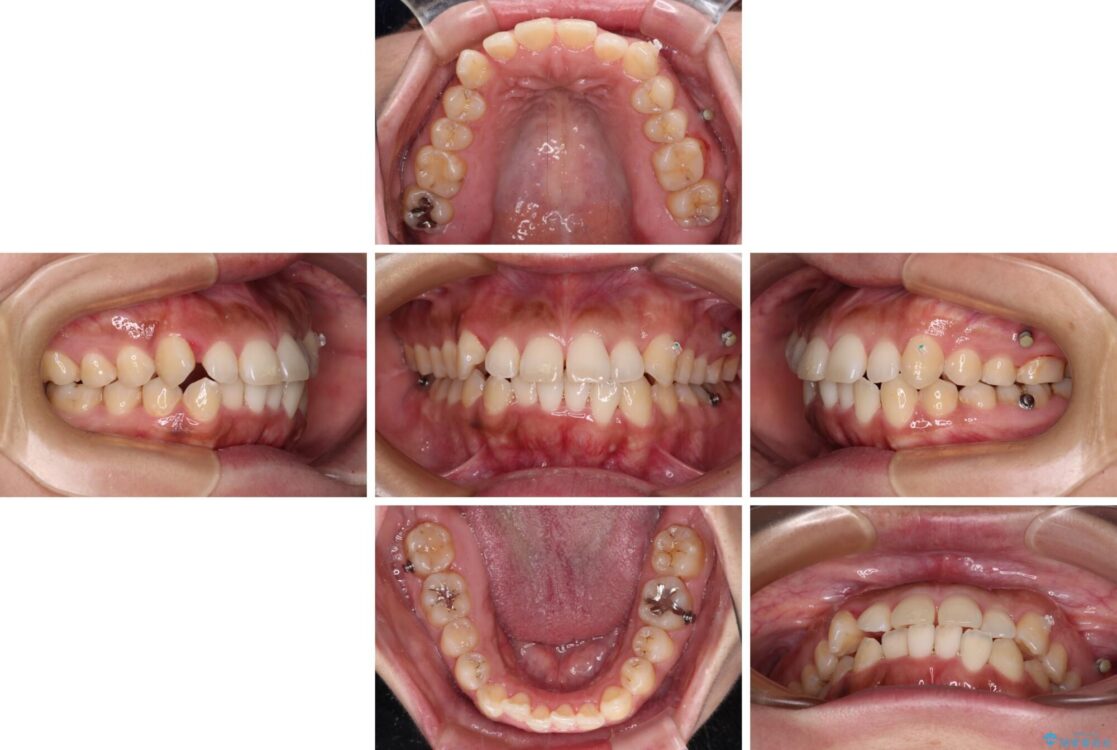

治療途中

• 【モニター】カリエール・ディスタライザーを併用した八重歯のインビザライン矯正 治療途中画像